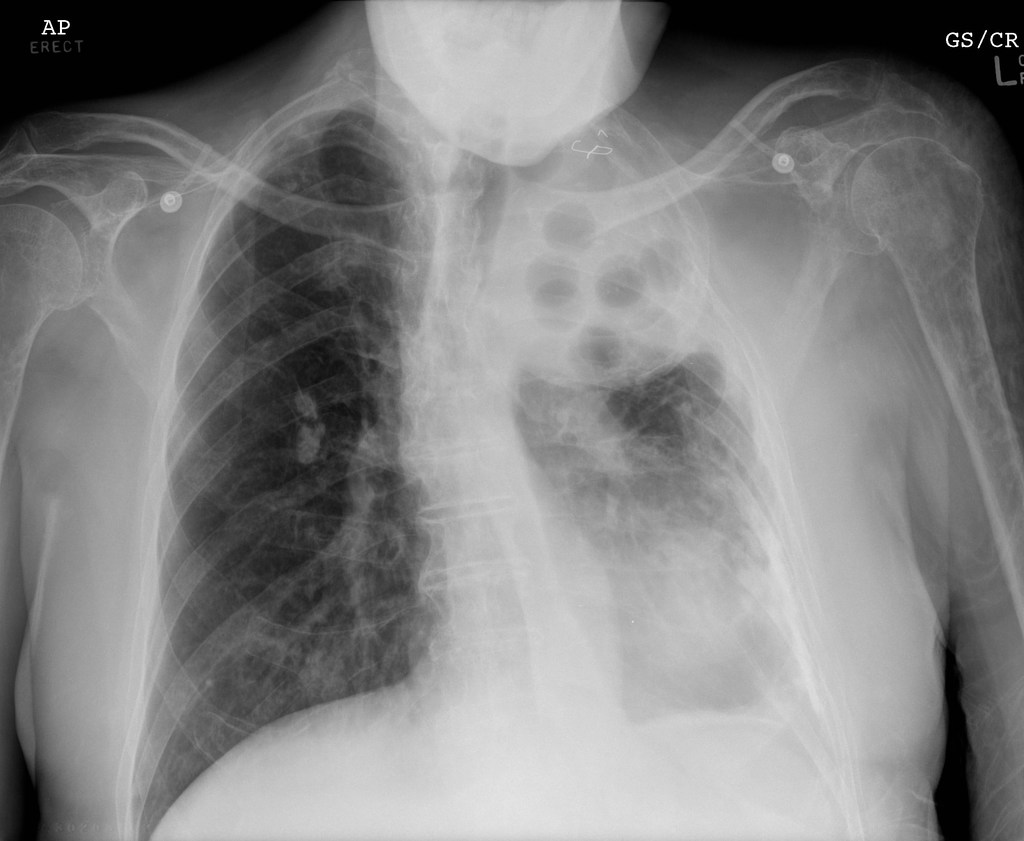

14. Plombage

Image source/RadiopaediaBefore there was any effective medicines for tuberculosis, plombage was used to teat the disease from the 1930s to the 1950s. Plombage would be the process of forcefully collapsing a lung , as scientist believed a collapsed lung could heel quicker. The treatment however carried numerous health risks, including infection and hemorrhages.